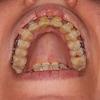

Мои опасения: Единица и двойка правые (на фото слева) стоят как-то не так. Мне кажется, что они не правильно развернуты вокруг своей оси (не знаю, как точнее выразиться). Однако за 3-4 последних месяца они совершенно не изменили свое положение. В связи с этим я сомневаюсь, что они двинутся хоть куда-то за оставшееся до снятия время. Дуга на них никак не действует. Как я думаю, нужно сделать что-то дополнительно. Может сепарацию, может как-то потянуть чейном или переклеить брекет. Не соображу никак. Однако орта ничего такого не планирует. Я реально в панике, что так и останется!! Я, конечно, брекеты снимать не дам))). Однако хотелось бы использовать время плодотворно, склонив орту к какому-либо действию с этими зубами.

Leta здравствуй, видимо не выходит на фото до конца передать. Но там режущие края как-то отклонены. Да и дуга стоит не ровно. Будто в месте стыка 1 и 2 завал внутрь. Как бы поворот не правильный. Не знаю ещё как объяснить ((

Leta спасибо!!! Вот это я ей скажу. Что попробуйте дугу изогнуть. Сделала поближе - проблемы для меня на той стороне, где проволока на брекет намотана

Мне кажется, что левая единица стоит под другим углом. Может попросить врача поменять её наклон? Такое ощущение, что корень нужно наклонить внутрь немного, а режущую часть - наружу.